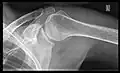

X-ray

Projectional radiography views of the shoulder include:

- AP-projection 40° posterior oblique after Grashey

The body has to be rotated about 30 to 45 degrees towards the shoulder to be imaged, and the standing or sitting patient lets the arm hang. This method reveals the joint gap and the vertical alignment towards the socket.[24]

- Transaxillary projection

The arm should be abducted 80 to 100 degrees. This method reveals:[24]

- The horizontal alignment of the humerus head in respect to the socket and the lateral clavicle in respect to the acromion

- Lesions of the anterior and posterior socket border, or of the tuberculum minus

- The eventual non-closure of the acromial apophysis

- The coraco-humeral interval

CR. shoulay film.

Transaxillary conventional radiography

Y-projection conventional radiography